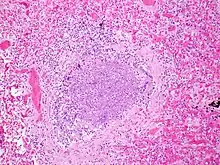

The term usually refers to acute viral bronchiolitis, a common disease in infancy. This is most commonly caused by respiratory syncytial virus[12] (RSV, also known as human pneumovirus). Other agents that cause this illness include human metapneumovirus, influenza, parainfluenza, coronavirus, adenovirus, rhinovirus and mycoplasma.[13][14]